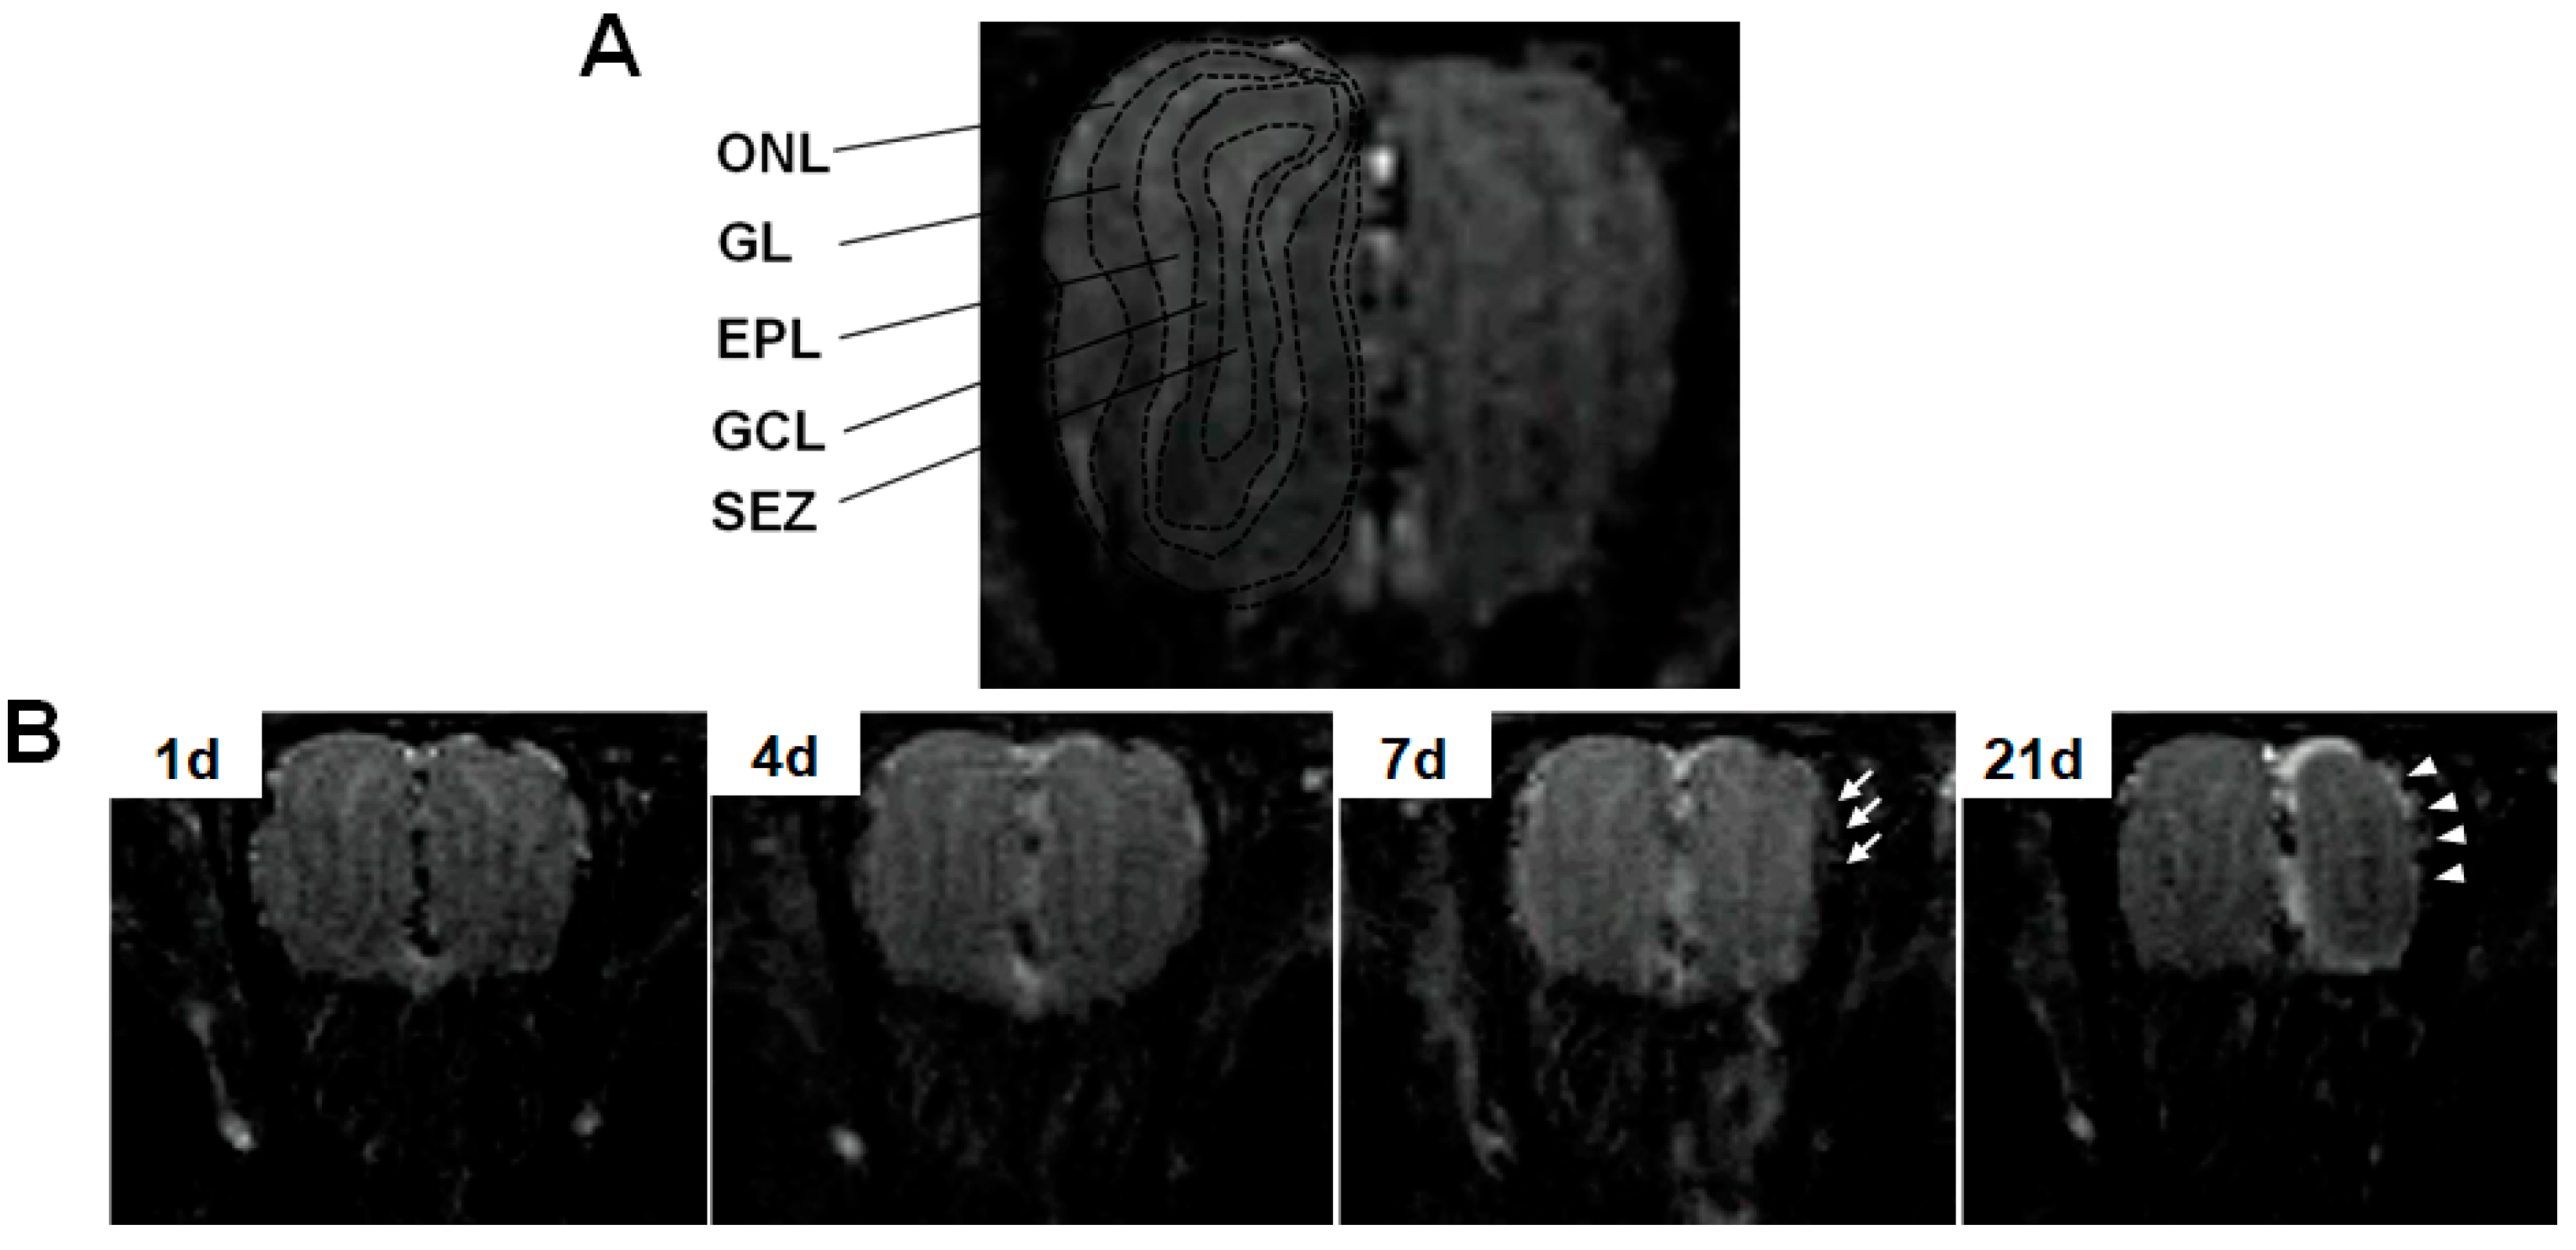

3.3. Structural Changes of the OE and OB